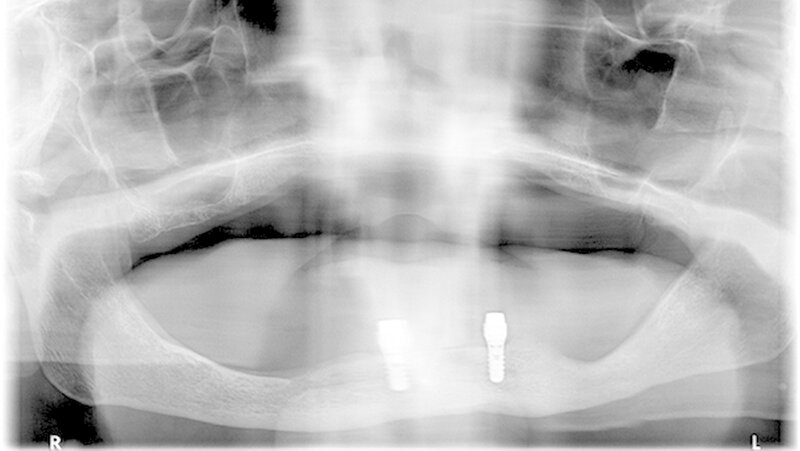

Die Patientenkohorte umfasste acht Männer und elf Frauen mit einem mittleren Alter von 85,7 ± 6,6 Jahre. Die 19 Patienten erhielten je zwei Implantate mit acht Millimeter Länge. Der Ernährungszustand (BMI und Blutmarker) und kognitive Zustand (MMSE) wurden analysiert. Zudem wurden die periimplantäre Sondierungstiefe und der Plaque-Index Score erhoben.

Im Ergebnis zeigte sich, dass die Implantatüberlebensrate nach fünf Jahren 94,7 Prozent betrug. Es gabein frühes und ein spätes Implantatversagen. Der Verlust von periimplantärer Knochenhöhe betrug im Mittel 0,17 mm pro Jahr. Periimplantäre Sondierungstiefe und Plaque-Index-Werte waren niedrig und stabil in den ersten zwei Jahren und danach kontinuierlich erhöht. Die Korrelationsanalyse zeigte, dass eine verminderte kognitive Funktion und Ernährungszustand kein besonderer Risikofaktor für einen beschleunigten periimplantären Knochenverlust sind.

Titel des Posters: Short Dental Implants Retaining 2-Implant Mandibular IODs In Very Old, Dependent Patients: Radiological and Clinical Observation up to 5 Years